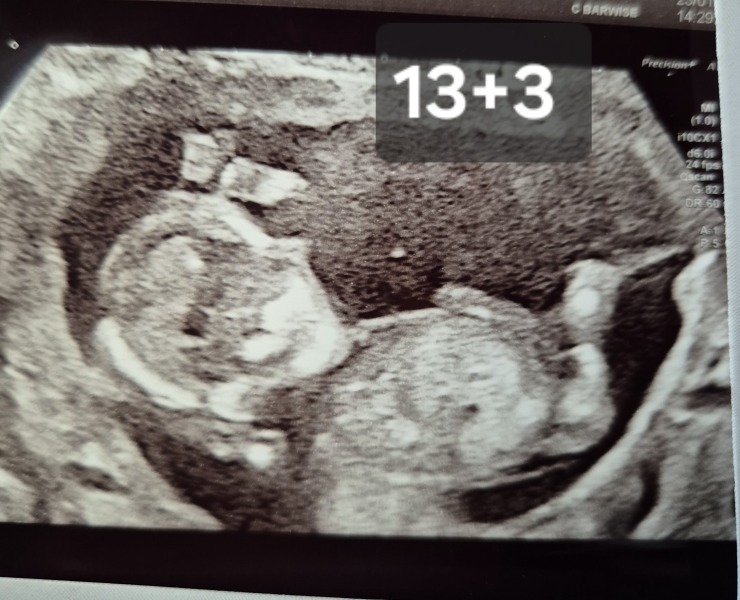

Please predict below image gender as per nub theory

Has anyone had nub theory be wrong?

Hey girlies can anyone take a look at my 12.3 week NHS scan pls.

Hi everyone, had a lot of boy guesses from nub theory. am I right in thinking I am having a boy?